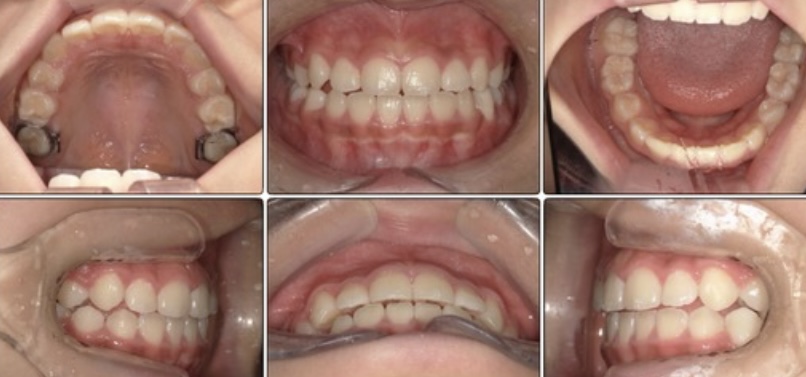

治療前 / 現在

治療開始時

現在

毎日の頑張りの成果があり、ここまで良くなりました。

ハの字になっていた上の前歯もまっすぐになり下の歯のガタつきも改善しています。